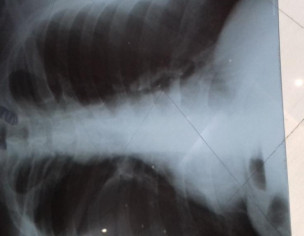

Attach Photo here: